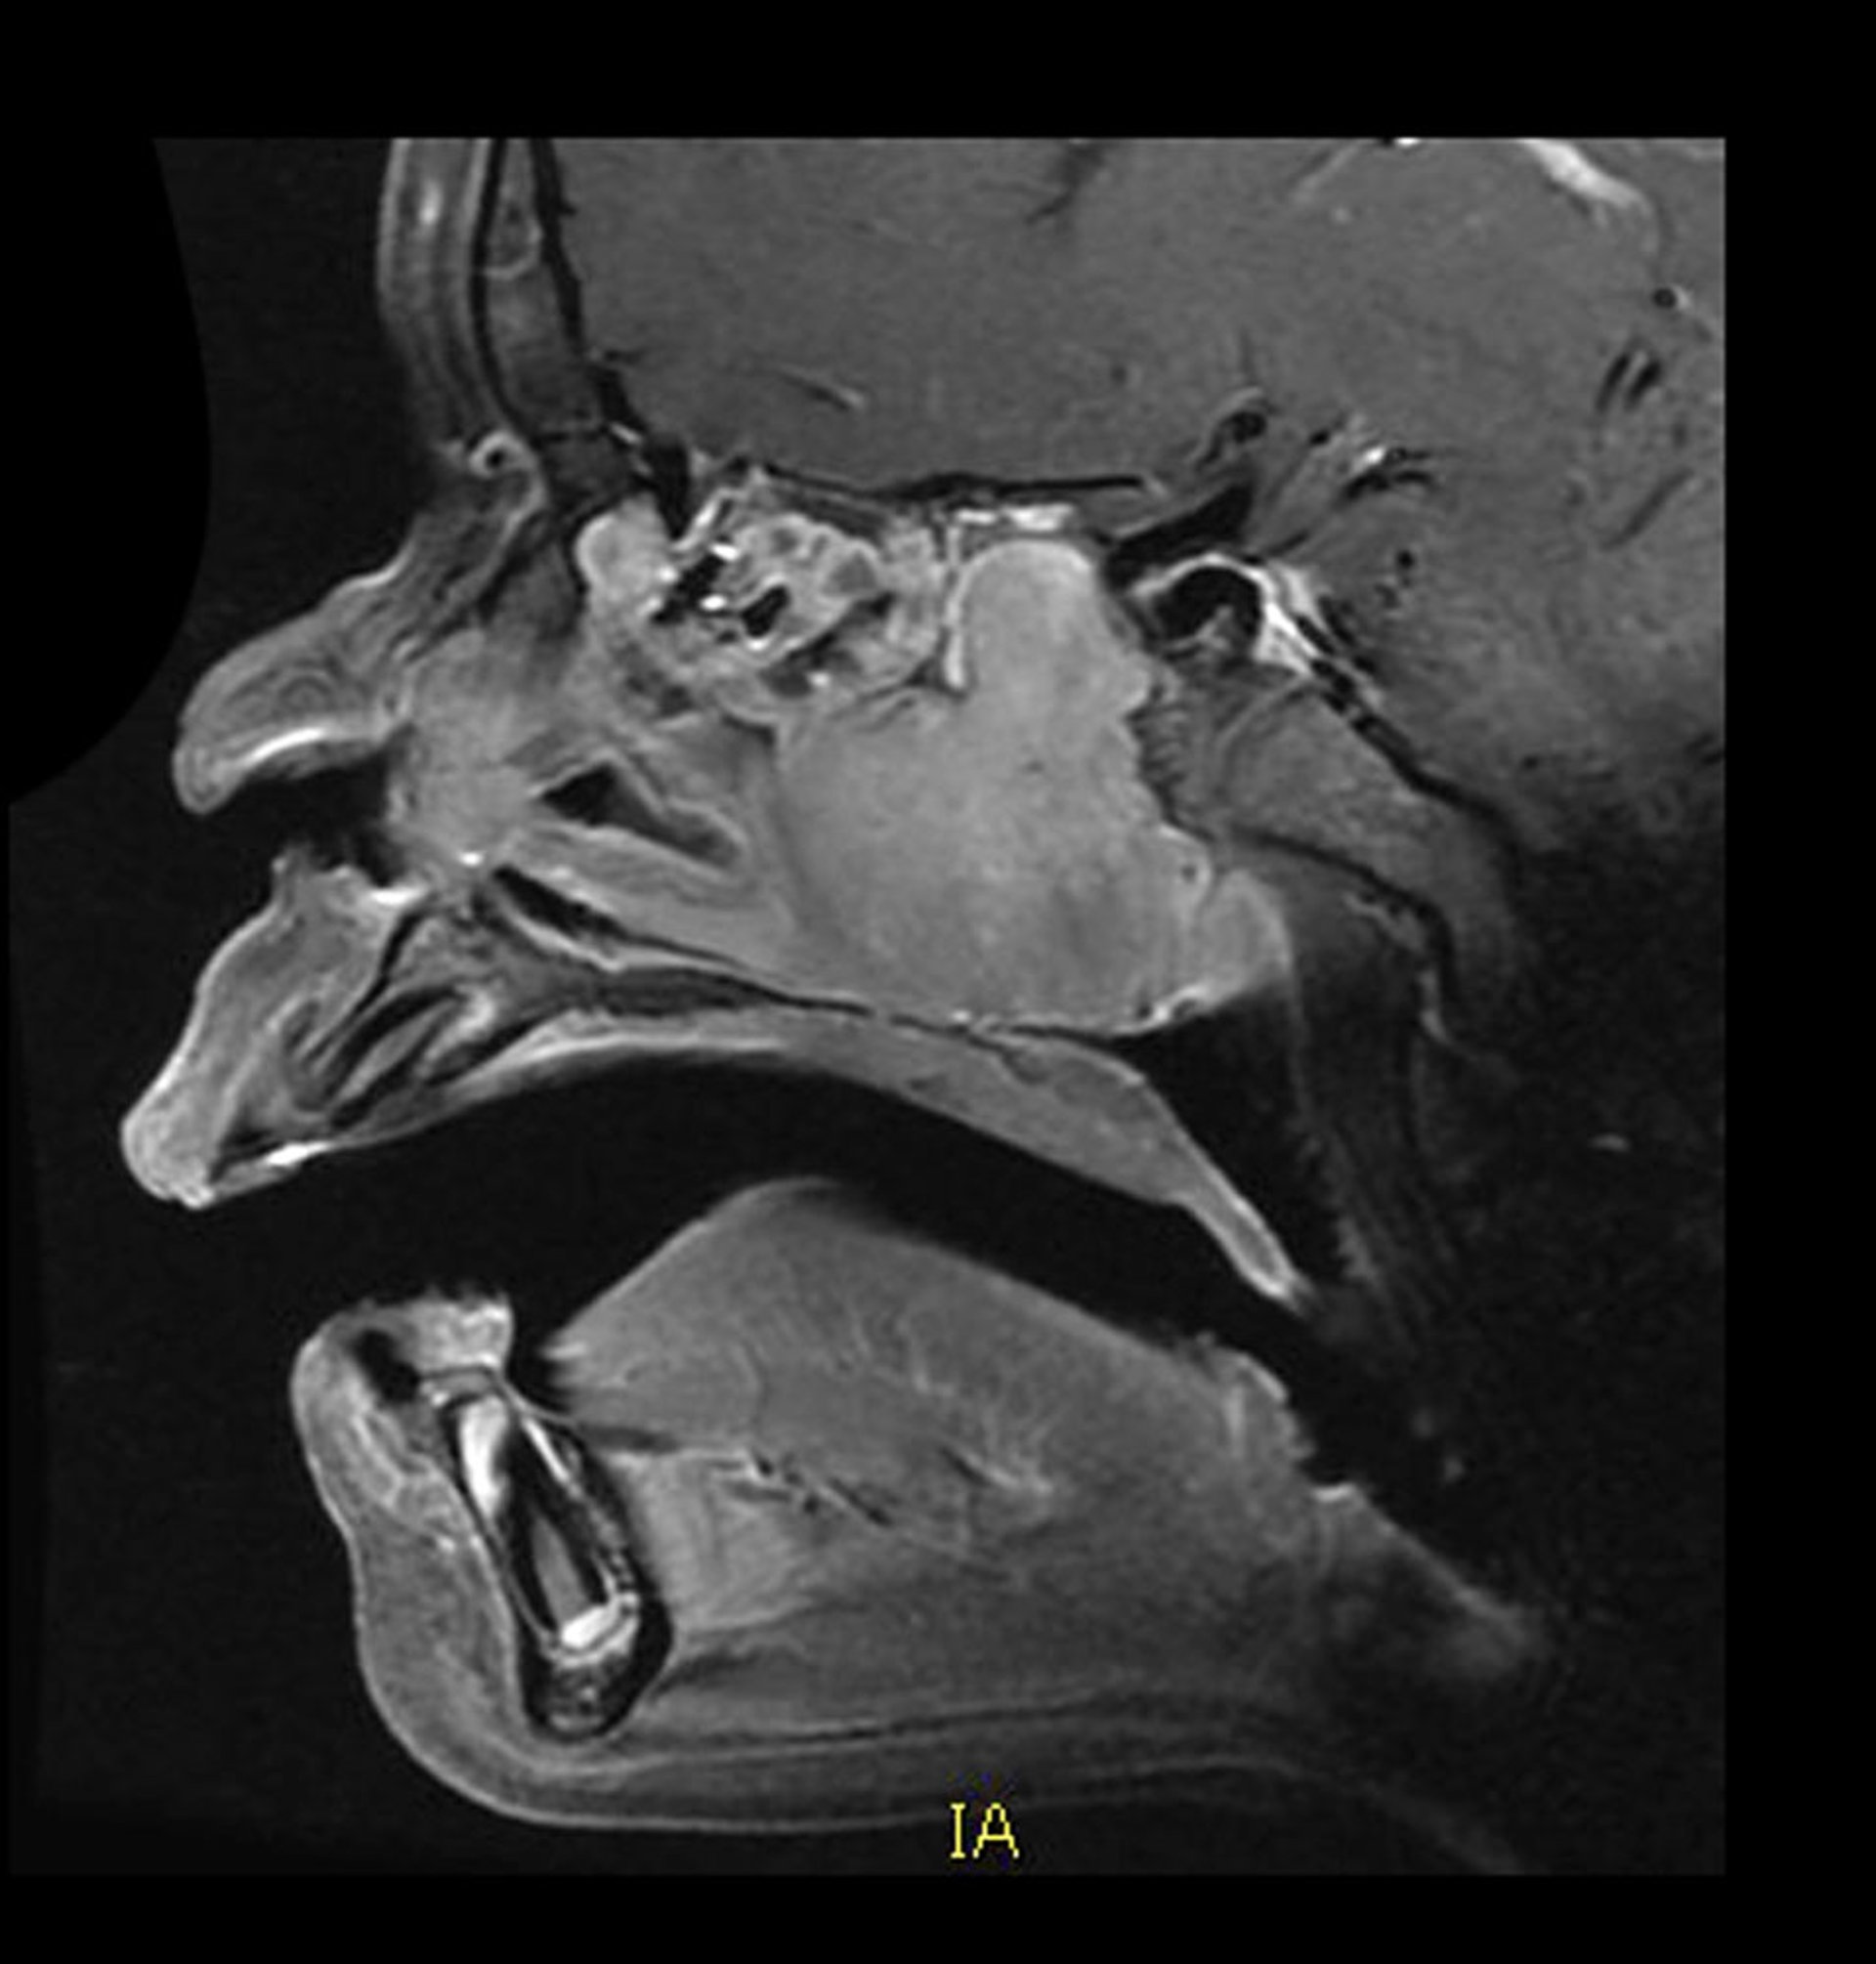

Dieses sagittale, kontrastverstärkte MRT zeigt die typische Lage und das typische Aussehen eines vaskulären juvenilen nasopharyngealen Angiofibroms. In der hinteren Nasenhöhle befindet sich eine homogen kontrastmittelaufnehmende Raumforderung, die nach hinten in den Sinus sphenoidalis hineinwächst. Auch die Zerstörung von Knochen ist damit assoziiert.